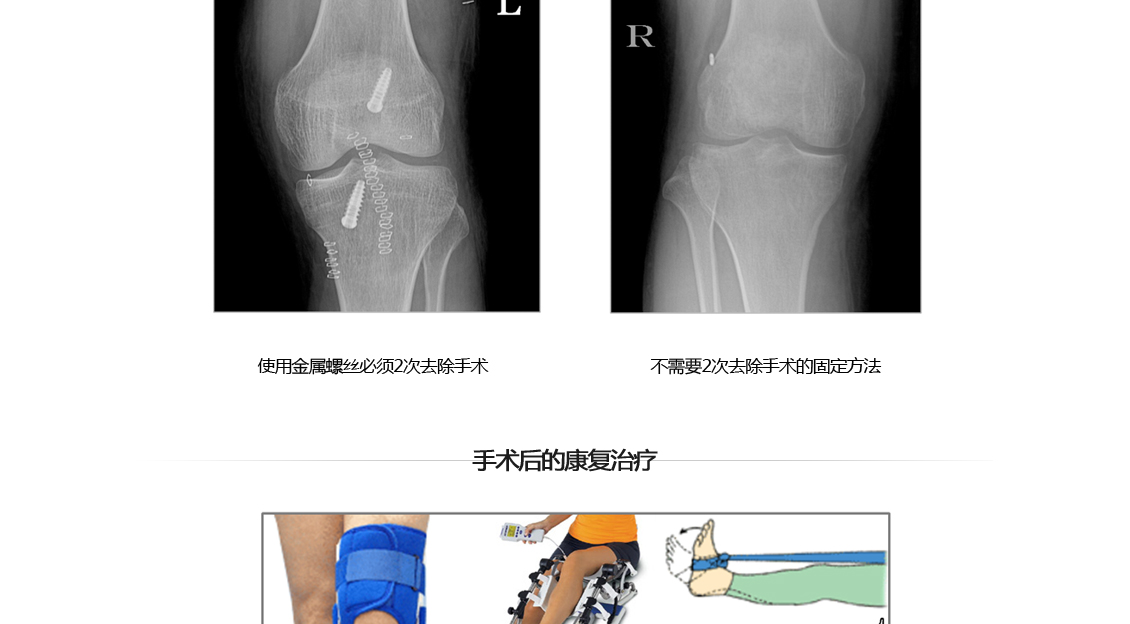

前十字韧带重建术